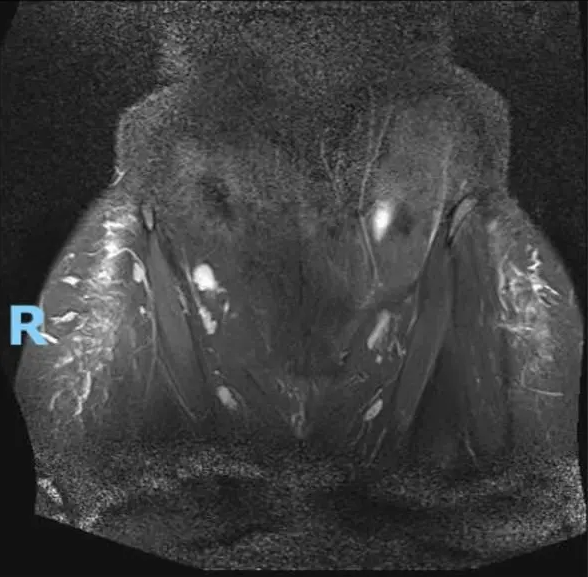

Ким Кардашъяан шиг болохын тулд өгзгөндөө дүүргэгч бодис шахуулсан эмэгтэй энэ төрлийн мэс ажилбараас татгалзахыг бүсгүйчүүдэд уриалжээ.

Тэрээр энэхүү хагалгаанд орсноос үүдэн жирэмслэх боломжгүй болсон бөгөөд байнгын өвчин намдаах эм хэрэглэх болсон гэнэ. Ким Кардашъяан шиг харагдахын тулд 1 сая ам.доллар зарцуулсан тэрээр өөрийгөө "мэс засалд донтсон" байсан гэдгээ хүлээн зөвшөөрсөн байна.

Энэ тухайгаа тэрээр "Би үргэлж л сайн ээж болохыг мөрөөддөг байсан. Харамсалтай нь дүүргэгч бодисын улмаас хүндрэл үүсч, энэхүү мөрөөдлөө биелүүлж чадахгүйд хүрсэн" гэжээ.

Уг бодис шууд хүнийг үргүйдэлд хүргэдэггүй ч хүндрэл үүссэн тохиолдолд ийн хариу урвал үзүүлж, нөхөн үржихүйн эрхтнүүдийн үйл ажиллагаанд сөргөөр нөлөөлдөг байна. Мөн хагалгааны явцад алдаа гарсан тохиолдолд үхэлд ч хүргэж болзошгүй байдаг тул энэ төрлийн хагалгаанаас татгалзахыг уриалжээ.